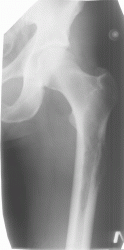

Патология костной структуры. Динамика. Ваше мнение?

Из анамнеза: 6 мес назад была травма. Не обращался,не лечился. Боли сохранялсиь,в последнее время усиливаются.

на саркому Юинга.

Биопсия это единственно правильно, на мой взгляд, больше данных за онкологию, но здесь обширный ряд: от той же саркомы Юинга (остеосаркомы, ЗФГ) до мтс, т.е имеет место некий весьма агрессивный процесс в виде остеолитической деструкции, инфильтрации кости. М.б. и поднадкостничная гематома, осложнившаяся остеомиелитом, но за полгода воспалительный процесс должен был как-то себя проявить...

Мне кажется, уже по первому снимку можно было онкологию выставлять.